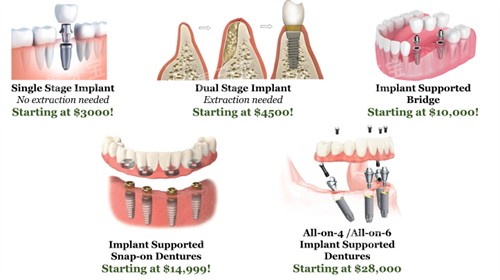

种植牙并非单一植体的置入,还涉及基台、冠部材料及手术辅助:

国产钴铬合金烤瓷冠价格:800元起

国产全瓷牙冠(二氧化锆)价格:1500元起

进口威兰德全瓷冠价格:3000元起

三维智能化导板设计价格:800元起

自体骨取骨术费用价格:1200元起

外源性骨粉(每0.25g)价格:1000元起

可吸收胶原蛋白膜价格:1500元起

在选择品牌时,建议患者关注“包括价格”,即是否包含了基台和全瓷冠,因为这些配件的品质直接影响种植牙的使用寿命。